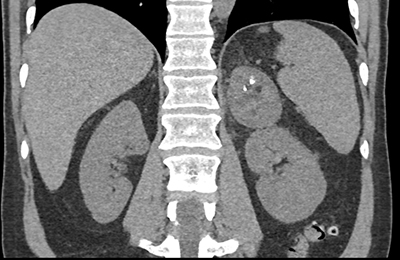

The workup for the patient incidental left adrenal mass is?

laparascopic adrenalectomy

CT or Ultrasound guided biopsy

an adrenal protocol CT

lesion is benign with no need for routine folllow-up